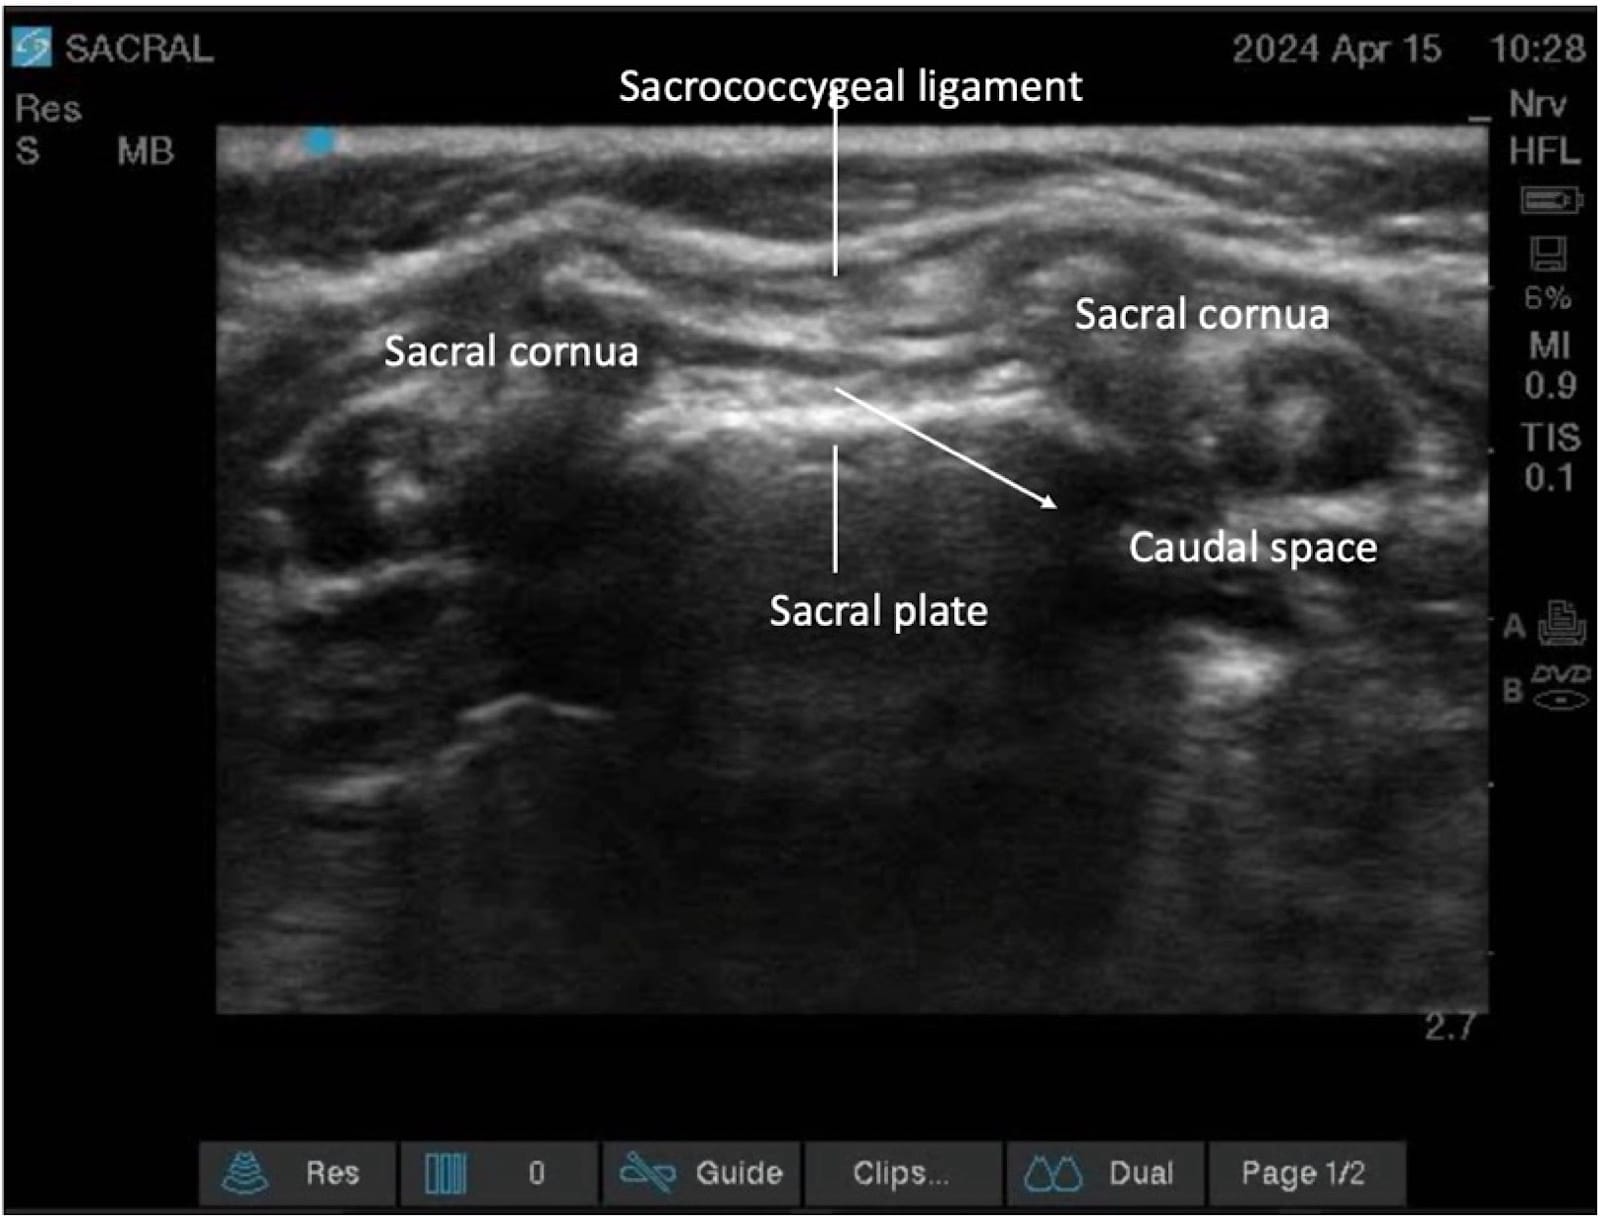

The sacral hiatus, a triangular opening at the lower end of the sacrum, is flanked on either side by bony projections known as the sacral cornua—remnants of the inferior articular processes of the fifth sacral vertebra. This opening is enclosed by the sacrococcygeal ligament. (Figure 2) Within the caudal canal lie epidural fat, the venous plexus, and the sacral and coccygeal nerves that form part of the cauda equina. The dural sac may also extend into this region, although its length is variable and decreases with age. (Figure 3)

Proper ergonomic positioning is essential, with the ultrasound screen and procedural field aligned along the operator’s natural line of sight. This facilitates precision and reduces operator strain. A high-frequency linear or hockey stick ultrasound transducer is used to optimize visualization of the superficial sacral anatomy. Key structures, including the sacral cornua, the sacrococcygeal ligament, and the caudal canal, should be clearly identified on the ultrasound image. The needle is then advanced in plane under continuous real-time USG to ensure accurate trajectory and safe entry into the caudal space. Alternatively, out-of-plane needle insertion during transverse scanning is an option. Adequate placement is confirmed by cephalad drug spread, dura displacement, and posterior epidural expansion. (Figures 10–15)